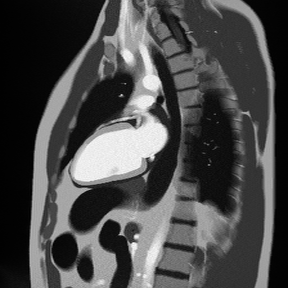

✅ Correct Planning for 2-Chamber Early Enhancement:

Correct Planning for 2-Chamber Sequence, early and late enhancement

✅ Correct Planning for 2-Chamber Late Enhancement (same as early 2-chamber):

2-Chamber Early Gadolinium Enhancement – Correct Image Example:

2-Chamber Early Gadolinium Enhancement – Correct Image Example

Things to Look for in 2-Chamber Early Enhancement:

• Dark zones within bright areas indicate MVO

• Both blood pool and myocardium should appear bright

• MVO typically occurs in the core of large infarcts

• Size and location help predict recovery potential